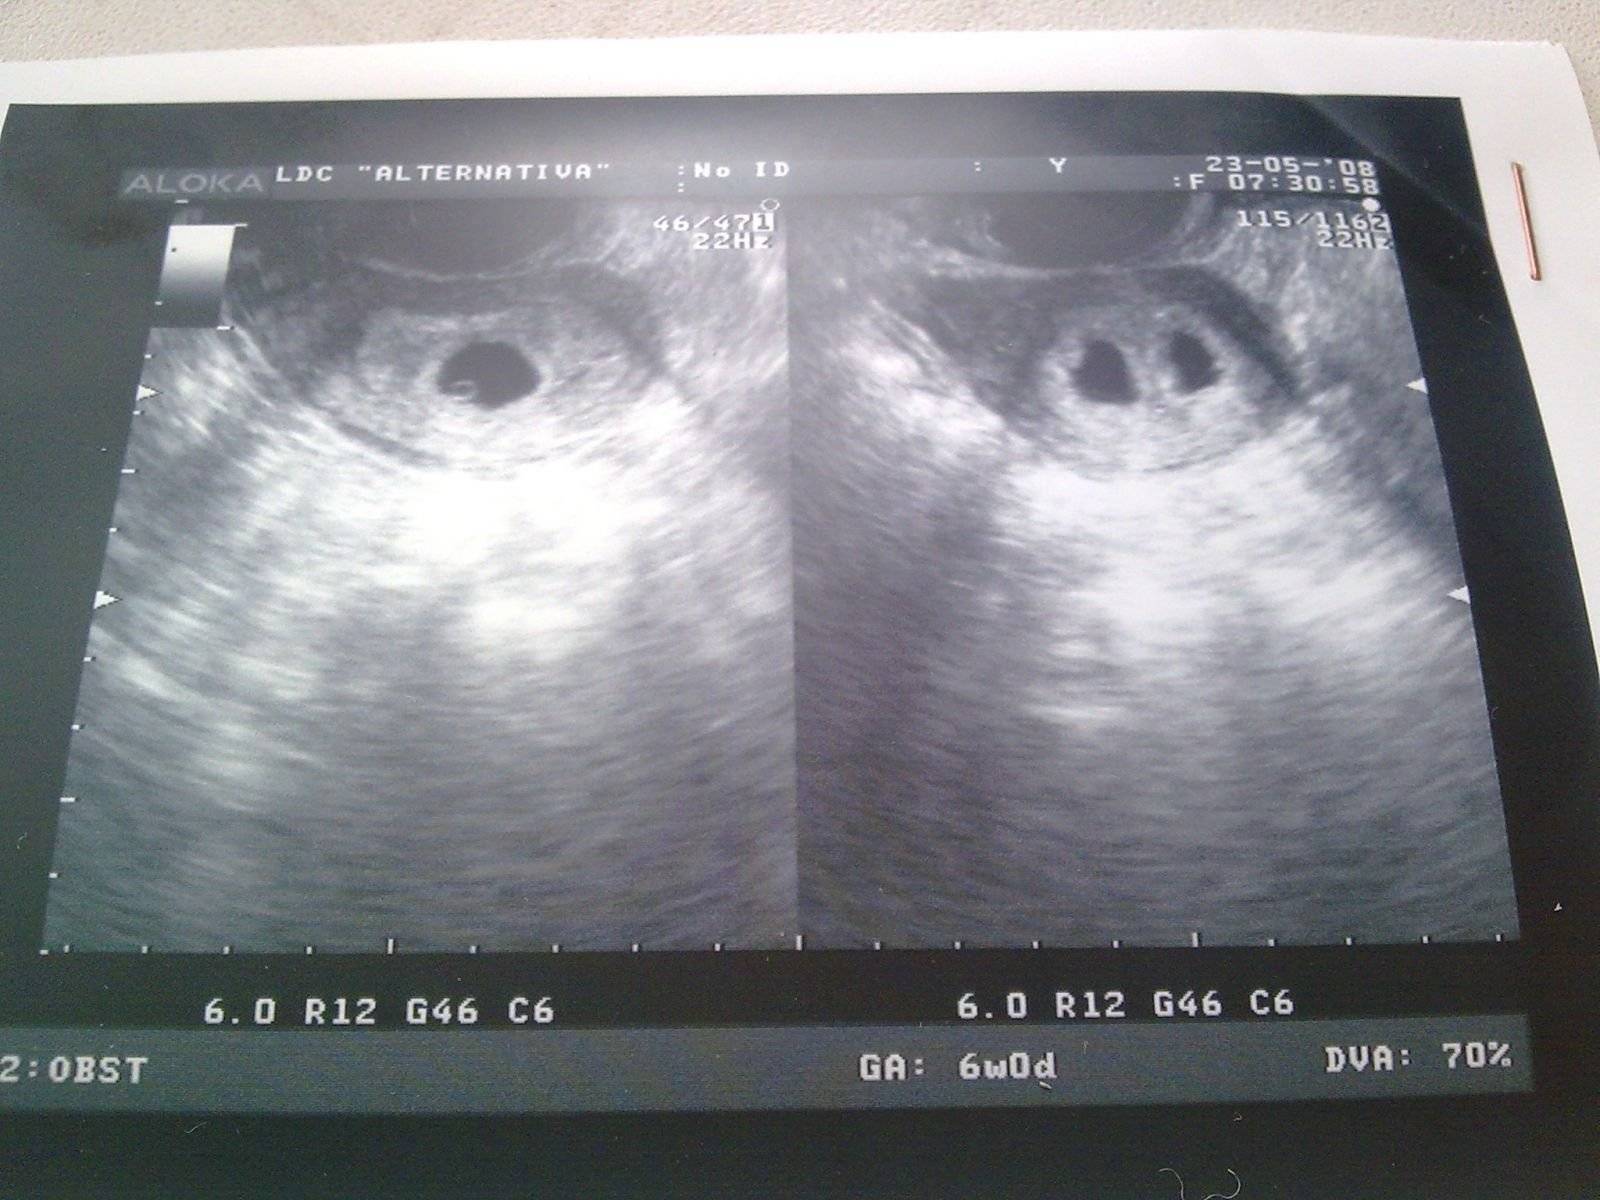

УЗИ двухплодной беременности на 5 неделе: Подборка изображений

Раздел: Калейдоскоп образов